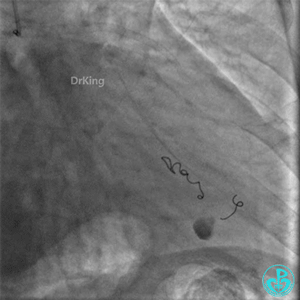

再次上台造影,钝缘支分支远端弹簧圈封堵处仍然有造影剂外漏。

明胶在血管怎么降解并发症丨前降支CTO同侧逆向开通时侧支血管破裂,弹簧圈联合明胶海绵封堵_https://www.jmylbn.com_新闻资讯_第48张

明胶在血管怎么降解并发症丨前降支CTO同侧逆向开通时侧支血管破裂,弹簧圈联合明胶海绵封堵_https://www.jmylbn.com_新闻资讯_第49张

心包穿刺引流。

明胶在血管怎么降解并发症丨前降支CTO同侧逆向开通时侧支血管破裂,弹簧圈联合明胶海绵封堵_https://www.jmylbn.com_新闻资讯_第50张

2根导丝进入到钝缘支分支远端,1根导丝送入微导管,另外1根导丝送入2.5×15mm球囊,2.5×15mm球囊远端Marker与微导管齐口(自制OTW球囊),经微导管缓慢推注明胶海绵糊。

明胶在血管怎么降解并发症丨前降支CTO同侧逆向开通时侧支血管破裂,弹簧圈联合明胶海绵封堵_https://www.jmylbn.com_新闻资讯_第51张

明胶在血管怎么降解并发症丨前降支CTO同侧逆向开通时侧支血管破裂,弹簧圈联合明胶海绵封堵_https://www.jmylbn.com_新闻资讯_第52张

钝缘支分支远端破口完全闭塞。